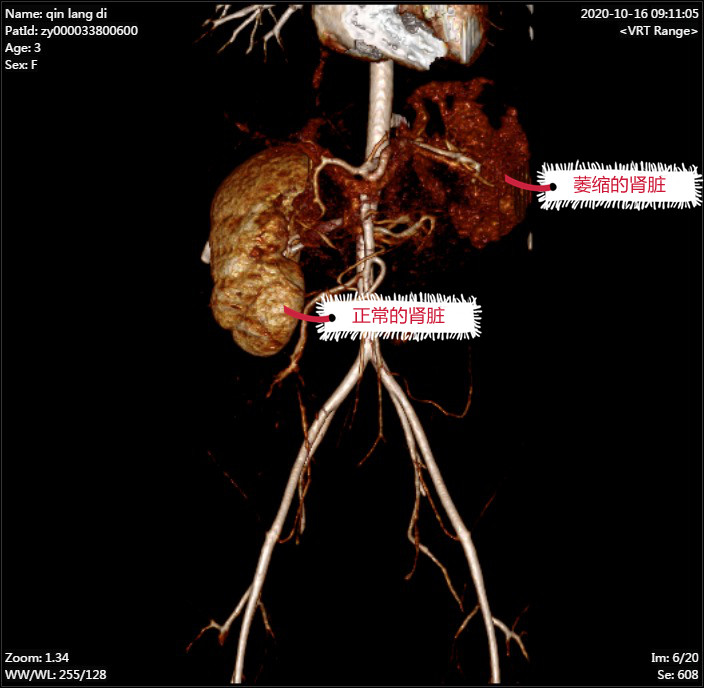

据了解,朗朗父母发现不给朗朗使用尿布湿后,孩子竟然天天漏尿,且伴有尿频、尿急症状,长达7个多月,给日常生活带来极大困扰,遂带他来到我院泌尿外科就医。经检查,朗朗被确诊为左肾异位伴萎缩伴左输尿管口异位,即先天性的输尿管开口异常。这是小儿常见的泌尿系统畸形,病因大多是胚胎时期输尿管芽发育异常,往往伴随其他器官发育不良,如重复肾、双重输尿管等,需要根据异位开口类型、引流肾脏功能选择合适的手术方式进行治疗。

朗朗的左侧肾脏不在正常位置,而且已经萎缩得极小,直径仅1.5厘米,已丧失基本功能,取得家属同意后,泌尿外科医疗团队决定切除左肾及部分输尿管。然而,如何精确的找到肾脏,减少不必要的损伤,又能达到术后快速康复及术口美观的效果,成了困扰泌尿外科医疗团队的一大难题。